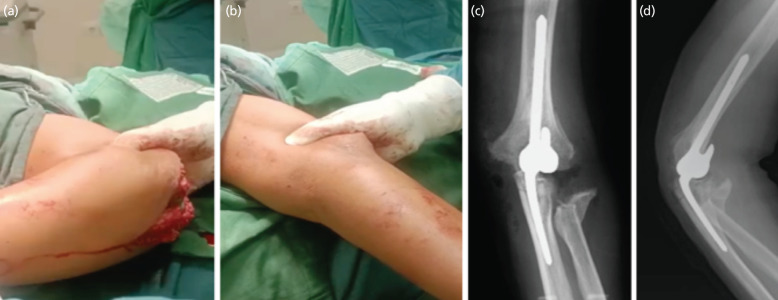

In young patients, the use of total elbow arthroplasty (TEA) is rarely preferred due to its high rate of mechanical failure. Poor compliance and psychological problems encountered may lead to increased difficulty in management. A 38-year-old male complained stiffness and pain on his left elbow. History of trauma was present 10 months ago, when he fell down from a tree of 6m high. Immediate closed reduction and immobilisation with backslab was performed, but he was lost to follow-up due to Schizophrenia. In physical examination, we found varus and recurvatum deformity with inability to flex the elbow beyond 30° and perform pronation. Plain radiograph and CT scan confirmed the terrible triad of elbow with callus formation. Total elbow arthroplasty with soft tissue release was then performed, resulting in satisfactory range of motion at one year follow-up. The management of neglected terrible triad of the elbow is challenging not only due to the bony problems, but also contracted muscles and fibrotic joint. TEA previously has been described in cases of inflammatory arthritis and degenerative arthritis, less in post-traumatic conditions especially in young patients. Though there is still scarcity in literatures discussing the burden of psychiatric problems in arthroplasty patients, but the existing literatures proved the correlation between psychiatric comorbidity with higher rate of post-operative adverse events. Total elbow arthroplasty can be considered as a surgical treatment for a young patient with neglected fracture dislocation of elbow with satisfactory result; however close post-operative monitoring and routine physiotherapy exercise should always be performed.